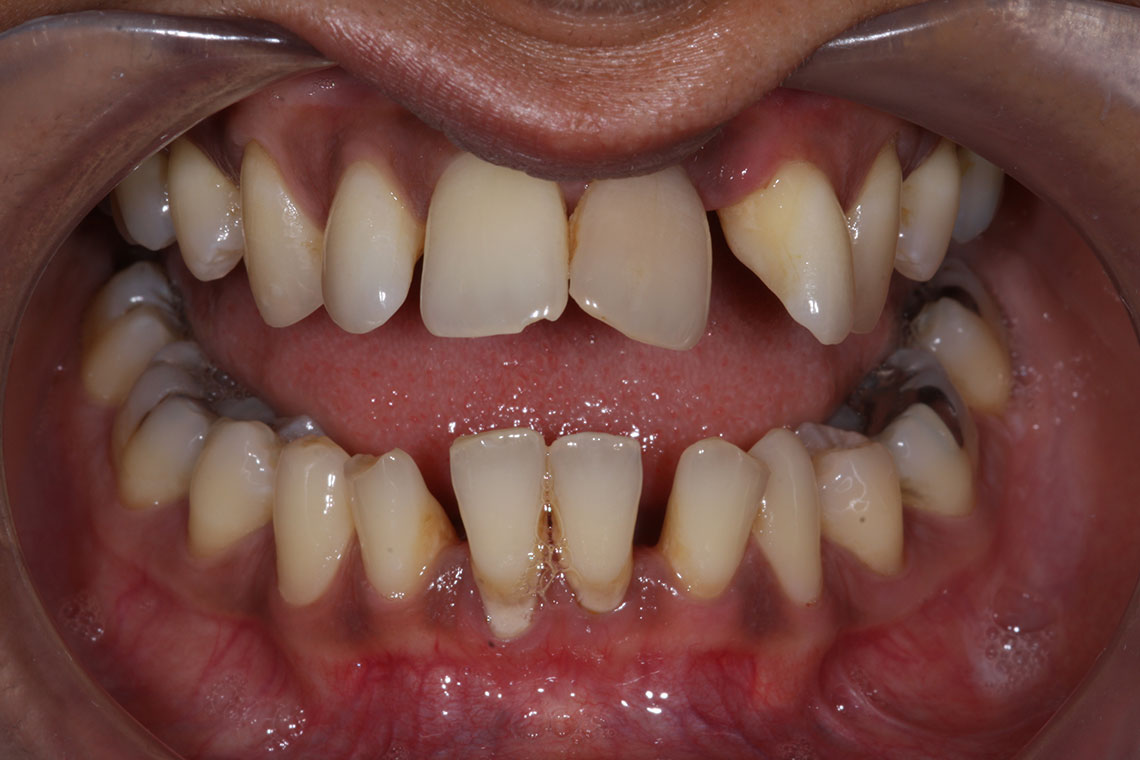

This lovely lady attended with very low confidence due to her teeth and smile. Gum disease and trauma had led to the teeth drifting. One of her front teeth was so loose that it needed to be replaced. We started by providing intensive treatment with our dental hygienist to treat the gum disease. Following this Invisalign® braces were used to align the teeth and the teeth were whitened. A dental implant was then placed to replace the loose front tooth and composite bonding was performed to the adjacent front tooth. The change in the patient’s confidence as a result of this work was breathtaking.